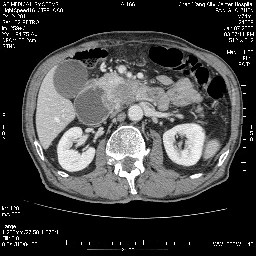

女,74岁,呕吐10余日

考虑来源于十二指肠水平段的恶性占位,侵及周围组织,特别是胰腺,可见区域淋巴结肿大,左侧下腔静脉畸形。

双肾多发小囊肿;左肾积水。

十二指肠水平段腔内占位伴梗阻,中等度较为均匀的强化,洗脱慢,区域淋巴结显示增多,符合腺癌表现。下腔静脉变异。

支持十二指肠腺癌伴梗阻.,下腔静脉发育变异.

十二指肠水平部腺癌伴梗阻并侵犯邻近结构。下腔静脉发育变异。

今日手术结果:胰腺钩突癌侵犯十二直肠,腹腔淋巴结转移.